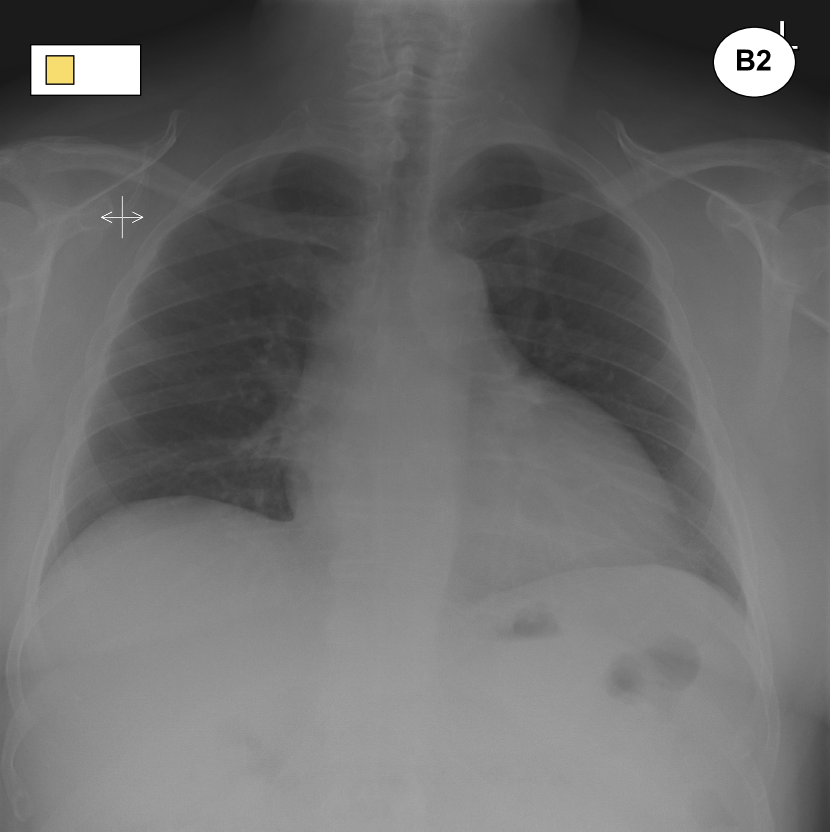

Figure 1: Examples of pairs of images that are placed close to each other in the learned embedding space shown in Fig. 3. A1 was incorrectly reported, but a second reading shows the presence of pleural effusion and a medical device, which justifies its proximity to A2. B1 was labelled as “normal”, but a second reading reveals some degree of cardiomegaly and, as such, the scan is placed close to B2. An extract from the original reports can be found under each image. Fig. 3 contains the legend for the labels.

Figure 3 shows a 222-dimensional representation of the 2,25222522,252 radiographs contained in the Golden Set. This representation was obtained by means of dimensionality reduction using a t𝑡t-distributed Stochastic Neighbor Embedding (t-SNE) [16], which effectively projects the 646464-dimensional embeddings extracted from the best model onto 222 dimensions for visualisation purposes. Remarkably, this projection shows that the normal exams are mostly concentrated in a well-separated cluster; moreover, other clusters of exams sharing similar abnormalities have also been identified.

The chest radiographs marked with a circle can be seen in Figure 1. These are two examples of radiographs that were originally labelled as normal but ended up being placed away from the cloud of normal exams. A second reading of these exams has revealed unreported abnormalities thus confirming that their position within the embedding was justified.

Figure 3: 222-dimensional embedding of all chest radiographs contained in the golden dataset learned through the ML2+ loss and visualised via multi-dimensional scaling. Each exam is represented as a point with different shapes and colors to identify multiple labels. Well-separated cluster of “normal” radiographs (green triangles) and exams featuring an enlarged heart are clearly visible. See Fig. 1 for the circled images.